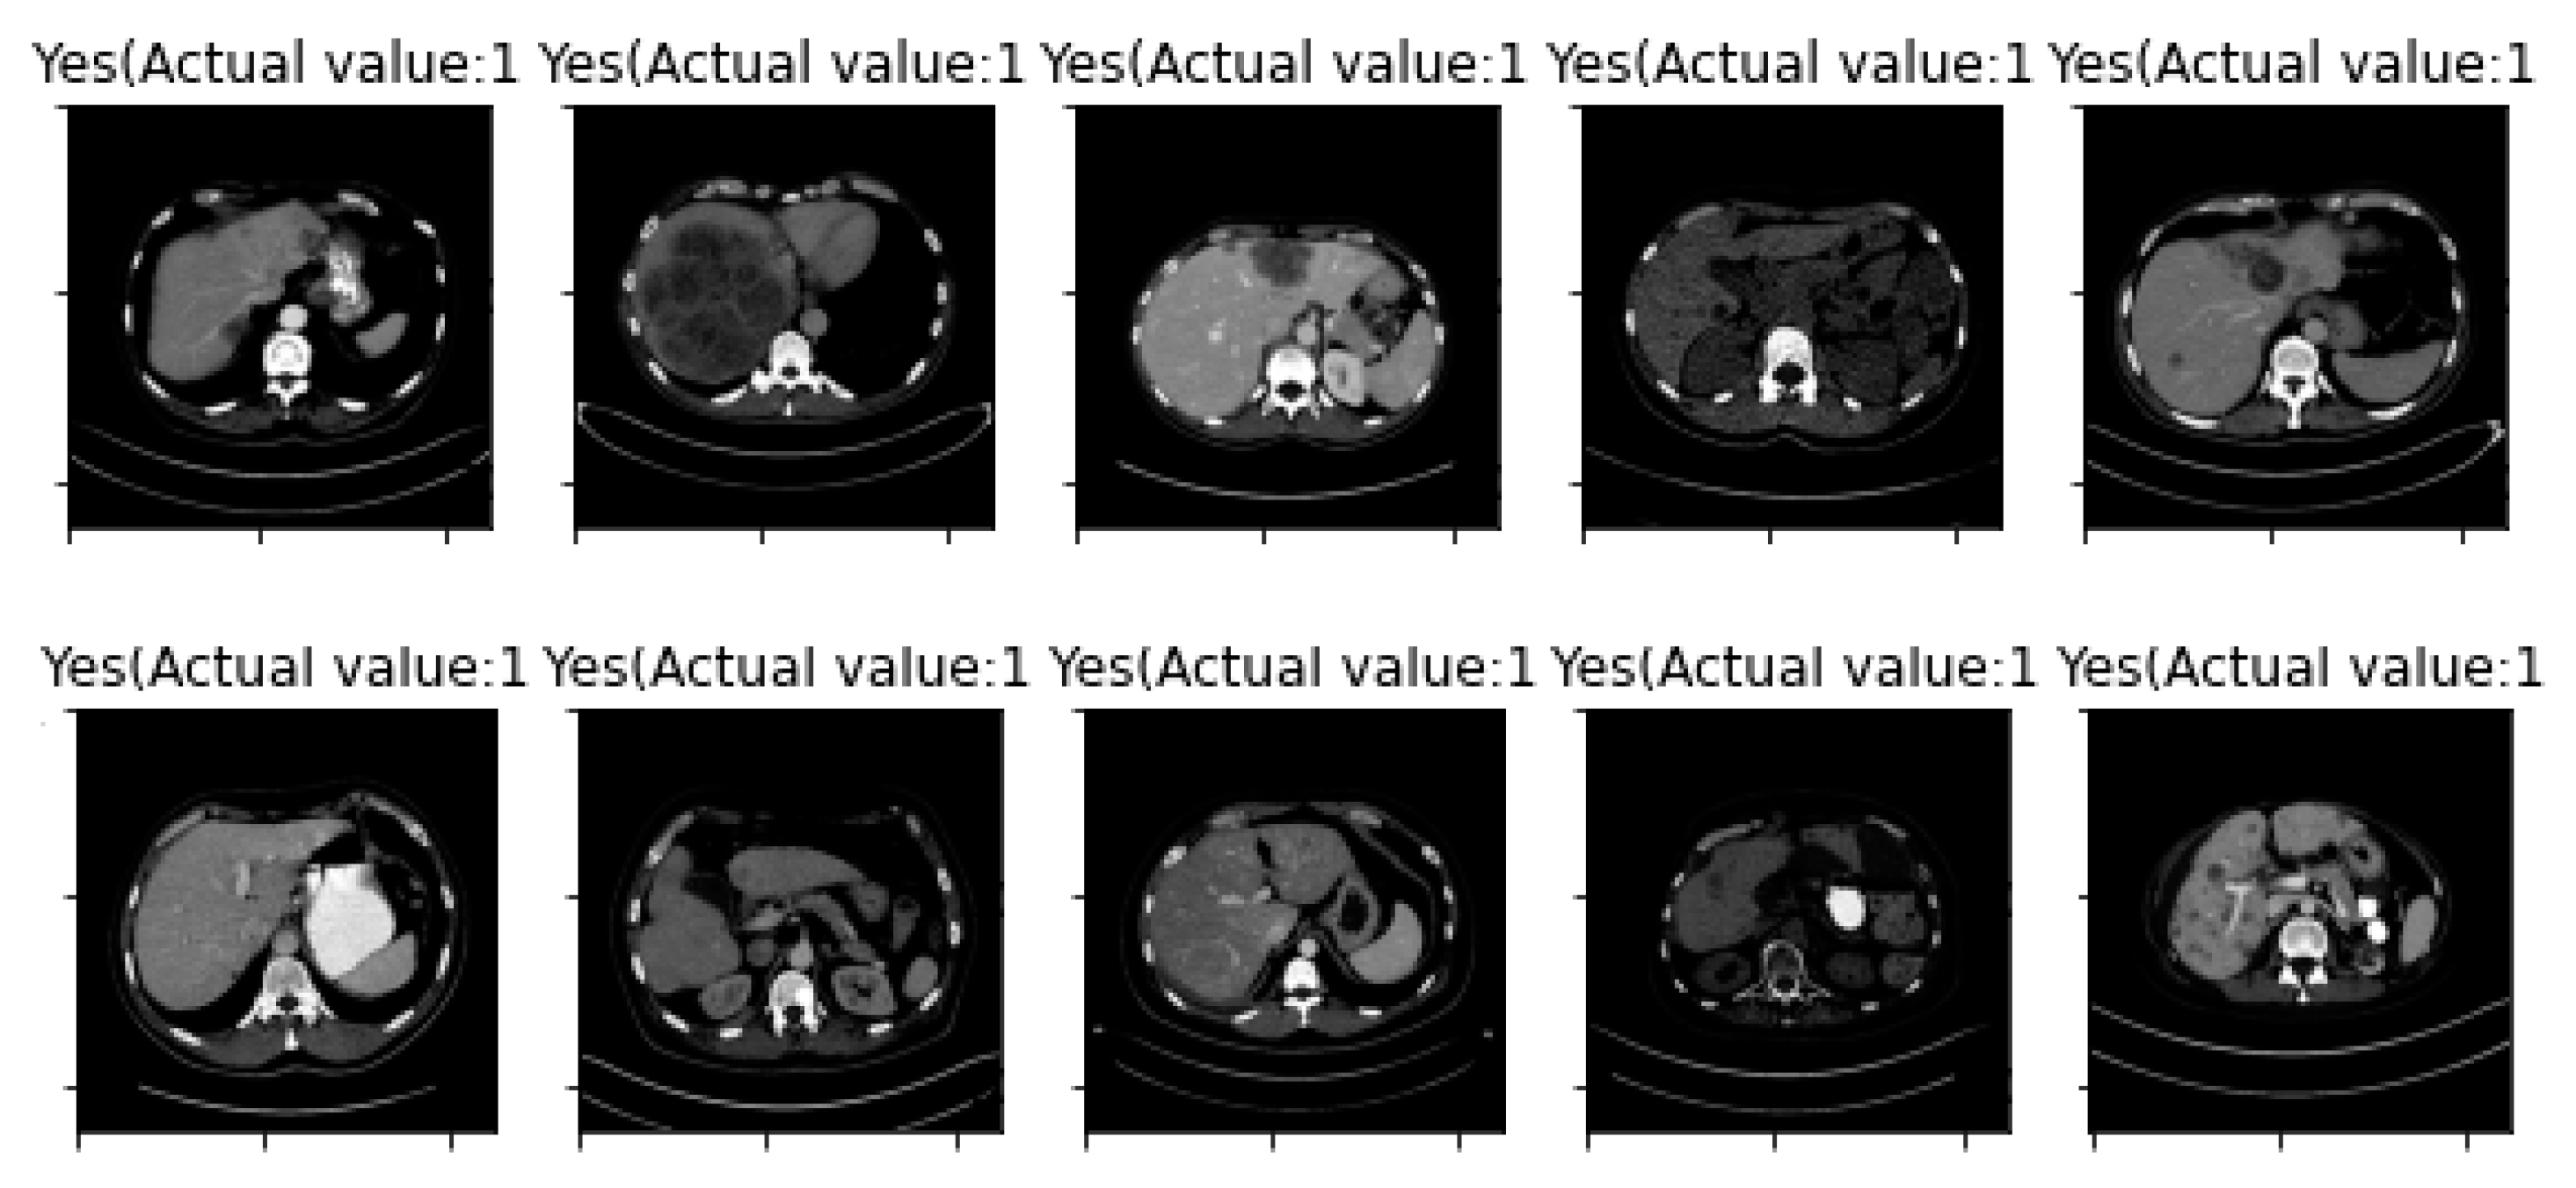

| Image Number | Overlaid Image | Deep Lesion Label | CNN Result | Clinical Radiologist’s Diagnosis | Grad-CAM Helpfulness |

|---|---|---|---|---|---|

| 11 | ![]() | Has Tumor | Has Tumor | No Tumor (Cyst) | Some |

| 12 | ![]() | Has Tumor | Has Tumor | Has Tumor | Yes |

| 13 | ![]() | Has Tumor | Has Tumor | No Tumor | Yes |

| 14 | ![]() | Has Tumor | Has Tumor | No Tumor (Inflammation of the Biliary Tract) | Some |

| 15 | ![]() | No Tumor | Has Tumor | No Tumor (Cyst) | Some |

| 16 | ![]() | Has Tumor | Has Tumor | Has Tumor | Yes |